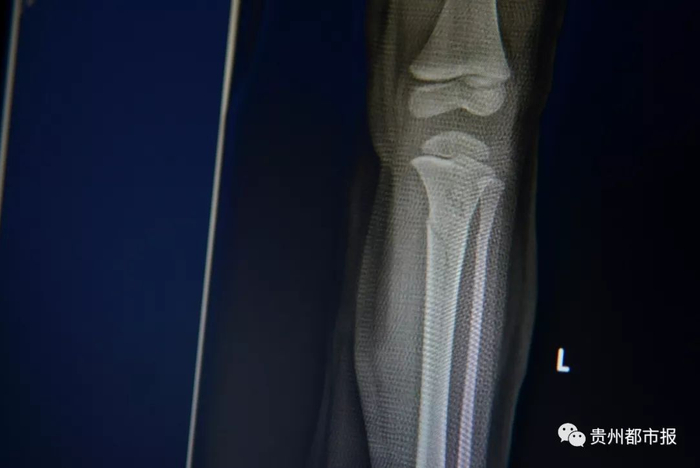

陈忠平被送到黔东南州医院重症监护室。冯宝宝入住医院骨科。经过检查,陈忠平颅内出血,冯宝宝左下肢骨折。

(因为陈忠平的保护,从高楼坠落的冯宝宝只有腿部骨折。)